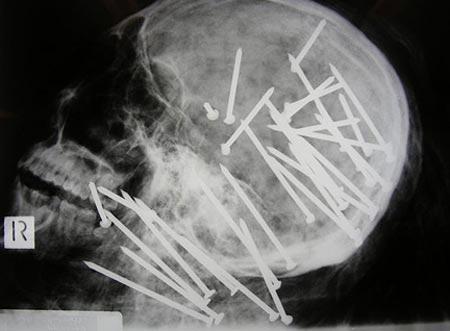

Şoke eden röntgen filmleri

Bu röntgen filmleri görenleri şaşkına çeviriyor!